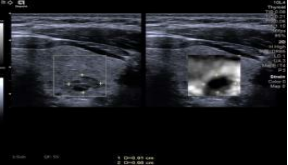

*应变弹性成像提供了一个简单的、定性的病灶与周国组织相对硬度的测量。